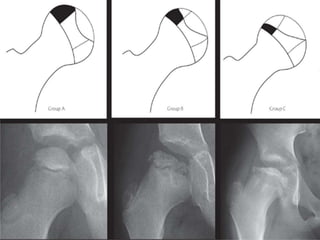

Herring Lat Pillar

 Group-A no involvement of the lateral

pillar, with no density changes and no loss

of height of the lateral pillar

 Group-B hips have lucency in the lateral

pillar and may have some loss of height ,

but not exceeding 50% of the original

height.

 Group-C hips are those with more lucency

in the lateral pillar and >50% loss of

height